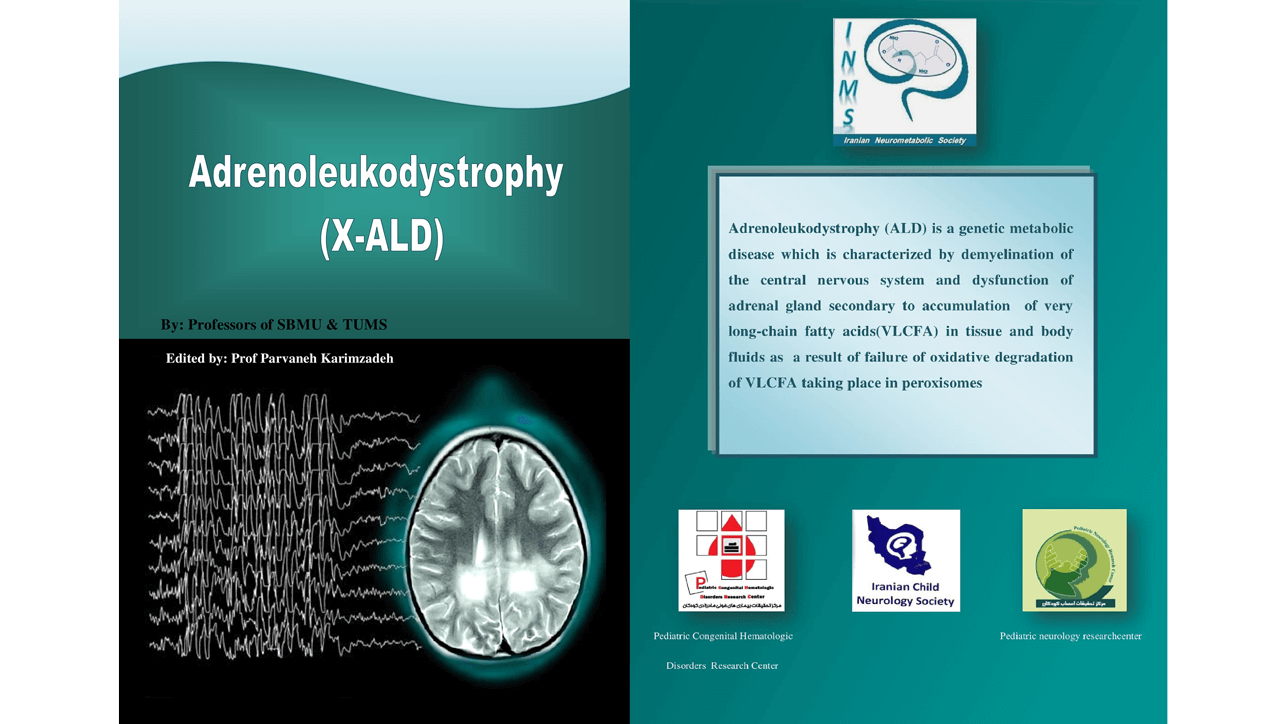

یازدهمین سمینار سالیانه نورومتابولیک ایران(Webinar) عنوان: لکودیستروفی ها